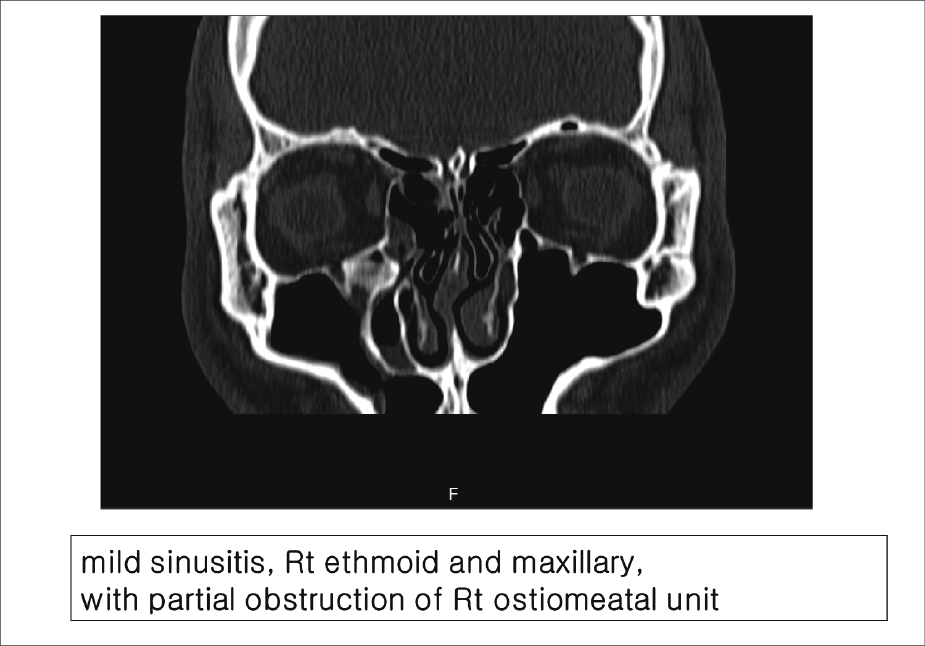

부비동염 동반 여부와 비중격의 모습을 확인하기 위해 P.N.S CT를 의뢰하여 촬영했고, 결과는 볼록면인 우측 상악동염, 사골동염을 동반한 만곡이였다.